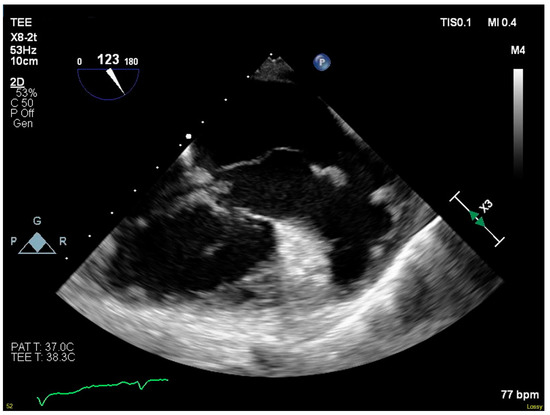

Blood cultures grew MRSA the following day, and antimicrobial therapy was narrowed to IV vancomycin. A transesophageal echocardiogram showed progression to severe tricuspid regurgitation with all three leaflets affected by destructive vegetations. The vegetation on the septal leaflet had grown to 5.6 cm and extended into the right atrium (Figure 1). She was transferred to our institution’s primary hospital for surgical management.

Figure 1. Serpiginous vegetation on septal leaflet of tricuspid valve.